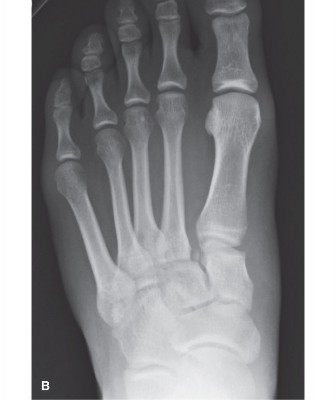

Figure 5–83 A: AP weight-bearing radiographs of the bilateral feet for comparison, showing diastasis of the

first intermetatarsal space and a positive fleck sign. B: Magnified view of AP weight-bearing radiograph showing the small avulsion from the medial base of the second metatarsal and lateral translation of the second base on the middle cuneiform—the medial borders of these bones should be in line on the AP view.